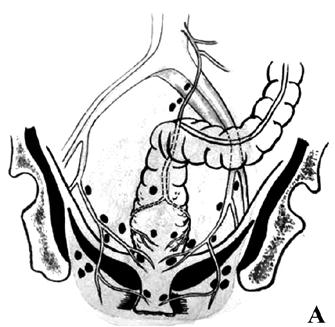

Брюшно‑промежностная экстирпация прямой кишки (операция Кеню‑Майлса) – показана при низколокализованном раке прямой кишки (ниже 5–7 см от ануса) и невозможности выполнения сфинктеросохраняющей операции. Операция заключается в удалении всей прямой кишки вместе со сфинктерным аппаратом, клетчаткой, лимфатическими узлами, дистальной частью сигмовидной кишки и формировании постоянной одноствольной колостомы (сигмостомы) на передней брюшной стенке (рис. 216).

Рис. 216. Брюшнопромежностная экстирпация прямой кишки: А – границы резекции;

Б – сформирована одноствольная колостома;

В – ушитая промежностная рана с дренажем в полости малого таза